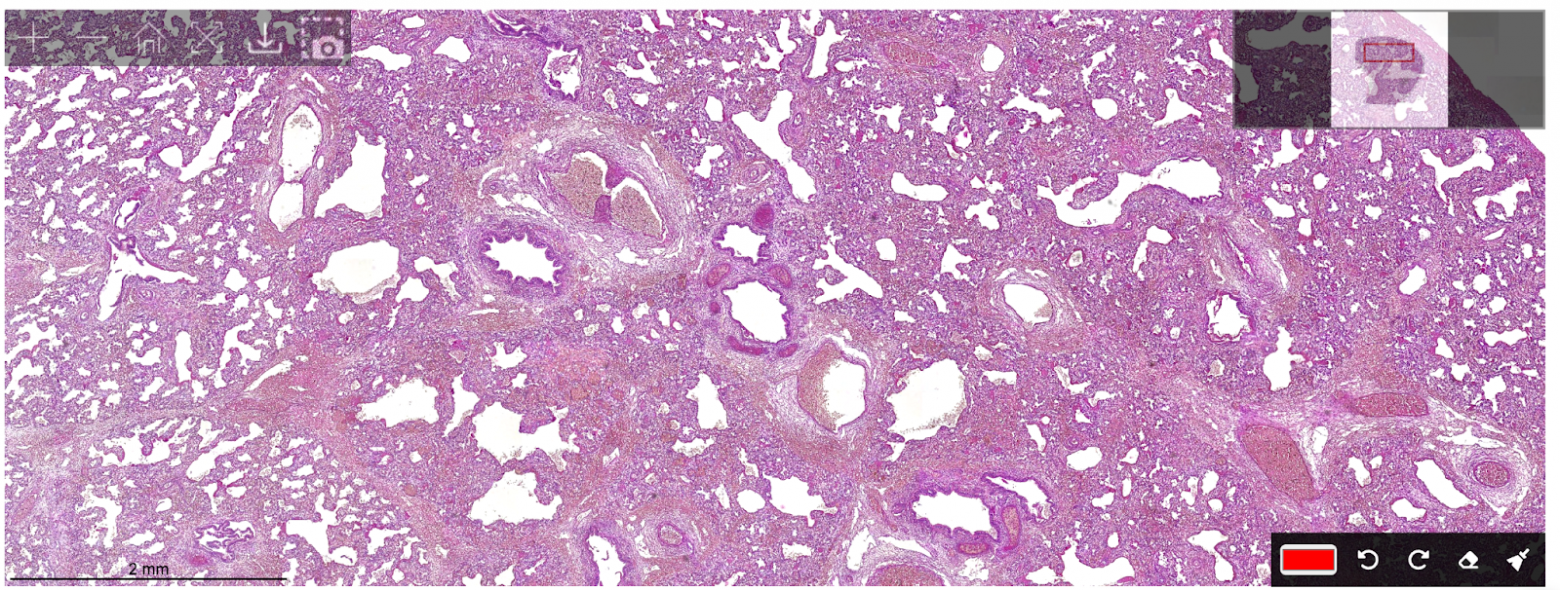

Поиск границ на увеличении 4x. Алгоритм проходит по всему стеклу, определяет область пятна и выдает карту границ на следующий этап. На выходе получается что-то вроде тепловой карты. Например, из изображения на низком увеличении слева мы получим матрицу, по которым уже построим шаги, чтобы двигаться на высоком увеличении:

Гистологическое изображение ткани на увеличении 4x